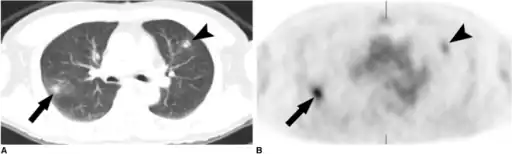

a,b)Simple pulmonary eosinophilia in an individual on both the CT and PET